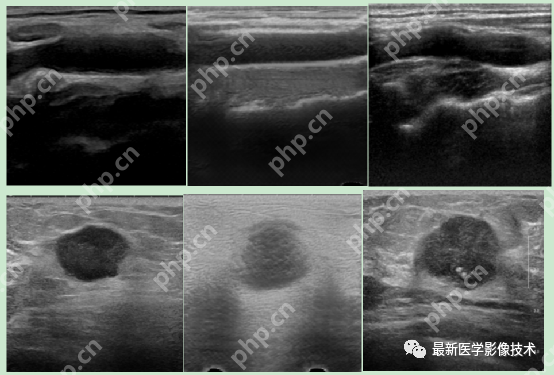

5、验证集部分生成结果

左图为低质量图像,中间为生成的高质量图像,右图为真实的高质量图像。